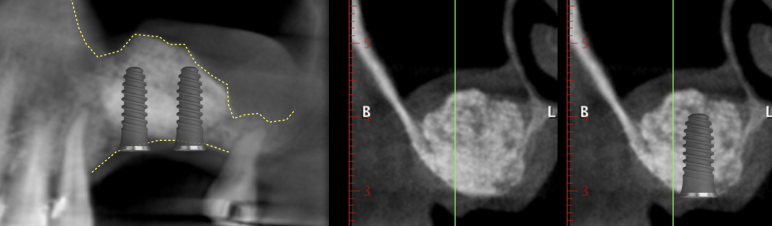

Elevación del seno maxilar

Procedimiento usado en la zona posterior del maxilar para reponer el hueso perdido. Es un procedimiento muy seguro que nos permiten colocar implantes donde antes no se podría.